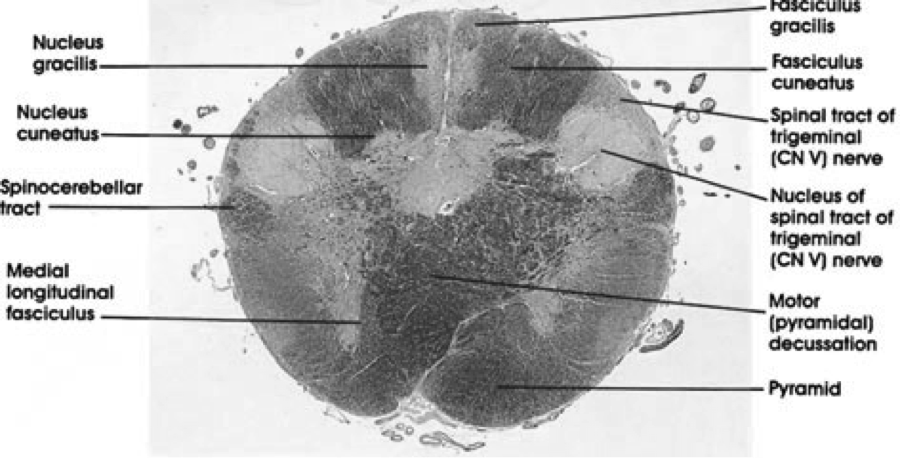

Medullary Pyramidal Decussation

Medullary Decussation